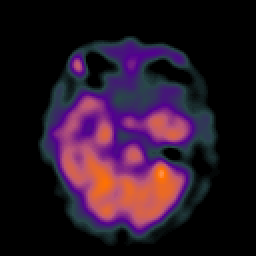

Hypertensive Encephalopathy, overlay -- Slice #8

[Home][Help][Clinical] Slice 8